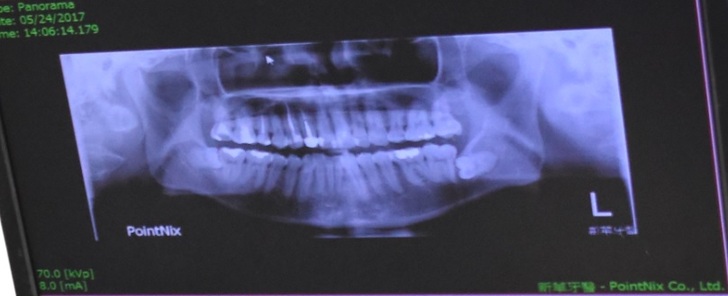

陳醫師看完老公的X光片後發現他的下顎大臼齒就是人人俗稱的智齒兩邊都是平躺著長

平躺著長!!對~~就是所謂的水平智齒

上次去的XX牙科看到老公水平智齒連動都不敢動~因為聽說很難拔

就因為那兩顆水平智齒清理不到才會三不五時蛀牙牙齦發炎